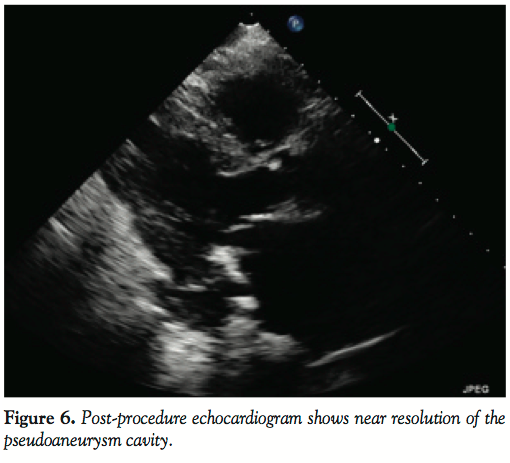

The patient did well after the procedure. She did not have further chest pain or dyspnea. She reported significantly increased exercise capacity. Cultures from the pseudoaneurysm cavity were negative. Follow-up echocardiogram 1 month later showed no communication between the left ventricle and previously closed pseudoaneurysm (Figures 6 and 7).